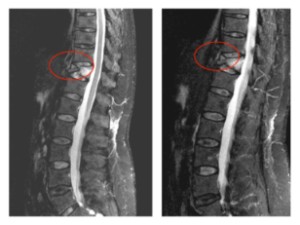

Fractura Vertebral Ejemplo de Caso Clínico

Resecció (corpectomia) i reconstrucció vertebral de fractures vertebrals complexes i conminutes

En els casos de les fractures més greus, com les fractures conminutes i les fractures d’esclat, un fragment del cos vertebral pot ficar-se dins del canal medular, provocant una compresió de les estructures neurològiques (estenosi del canal medular).

Quan amés n’hi ha un compromis neurològic, s’haruá de realitzar una resecció parcial o total del cos vertebral fracturat (corpectomia) per després reconstruir-lo reconstrucción mitjantçant d’una caixa somàtica expandible. La reconstrucció es sol completar amb una artrodesi percutànea instrumentada i cementada dels nivells adjacents a la fractura. La resecció de la vèrtebra (corpectomia) permet extrahir el fragment d’os qu’es trova al canal medular i lliberar les estructures neurològiques afectades. La reconstrucció amb una caixa somàtica permit descarregar la carga del pacient sobre la fractura i treure el dolor que aquesta li provoca.

Cas clínic d'una resecció (corpectomia) i reconstrucció vertebral lumbar en una fractura esclat de nivell L4.